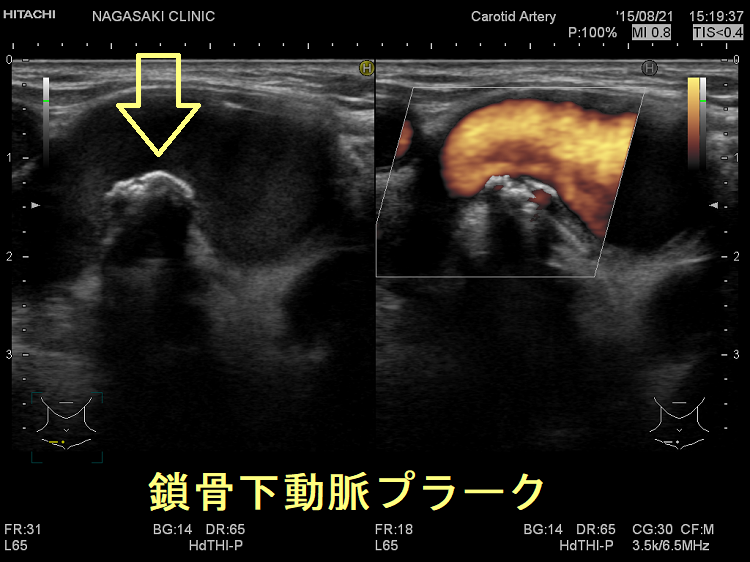

動脈硬化が進んだ血管にはプラーク(コレステロールエステルを大量に含んだ脂質の塊)(矢印)ができて、血管内が狭くなります。血管エコーでプラークを探す。動脈硬化した血管は硬くもろいため、大動脈では血圧に負けて大動脈瘤になることがあります(急性大動脈解離・大動脈瘤)。

(↓)デジタルハイビジョン超音波装置で見たプラーク。

死角、鎖骨下動脈プラーク